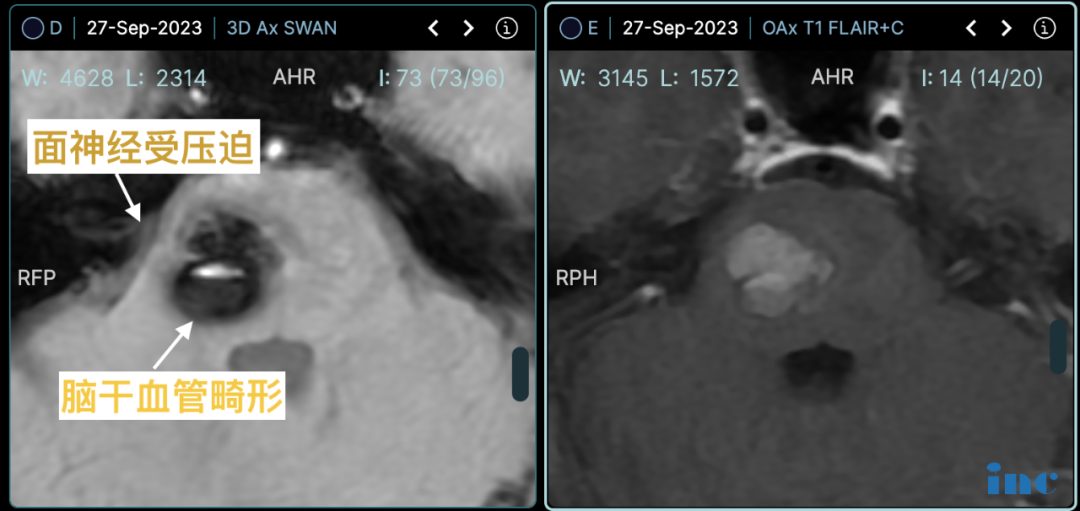

术前影像:面神经受压迫

除了海绵状血管瘤,我的面神经周围的一处血管形成了“剪刀”样的结构,长期压迫神经,导致了严重的面肌痉挛,半边脸经常不受控制地抽动。